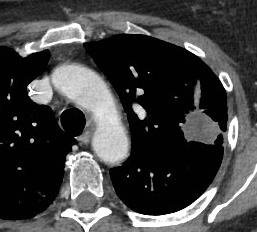

增强扫描提示复发

再射频消融治疗

再射频消融后复查